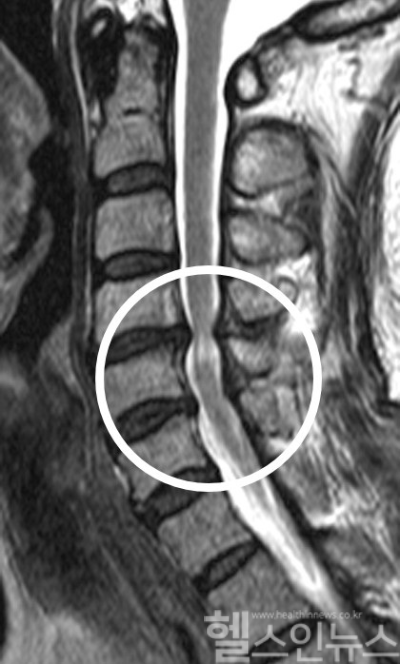

또한, 예측에 대한 각 변수의 영향을 SHAP 기법으로 분석한 결과, ‘수술 12개월째 JOA 점수’가 가장 중요한 영향을 미친 것으로 나타났다. 그 외에도 수술 6개월·1개월·3개월째 JOA 점수, BMI ▲수술 전 JOA 점수, 성별, 연령, MRI 뱀눈징후, 수술 전 보행상태 등의 순으로 많은 영향을 미쳤다.